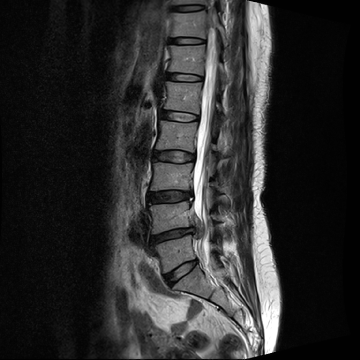

허리 디스크 수술 전·후

2022.09.28

2022.10.17

ㆍ환자 동의를 받은 자료이며, 이미지 사진은 실물과 다를 수 있습니다.

ㆍ모든 자료는 새움병원 자료입니다.